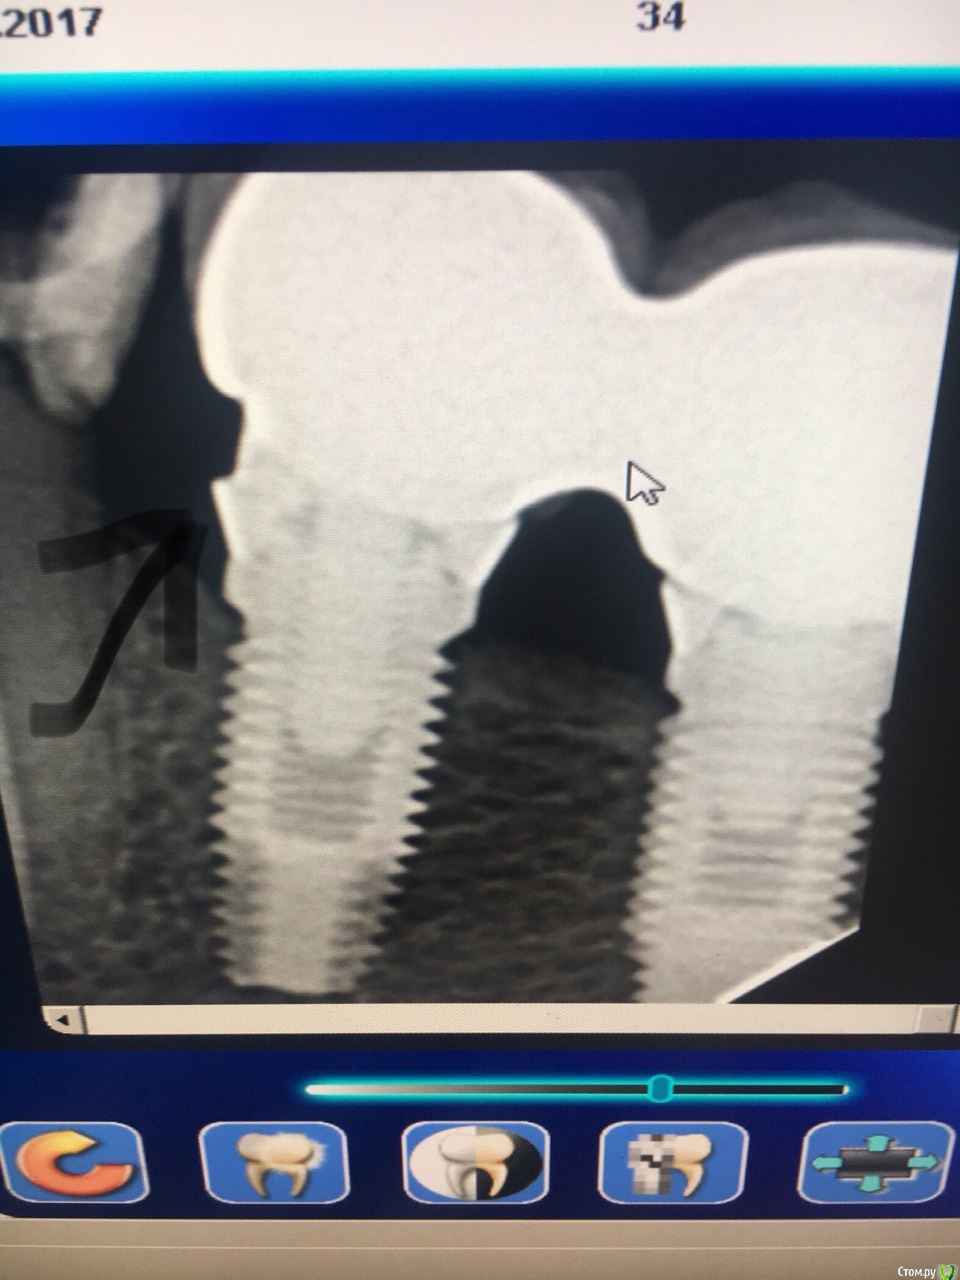

VladZp Опубликовано 17 октября, 2017 Поделиться Опубликовано 17 октября, 2017 Здравствуйте, имплантация и протезирование больше 7 лет назад, естественно название системы пац не знает и не помнит. требуется перепротезирование. может есть у кого догадки ? (из всего что я искал больше всего похож на нобель) Заранее огромнейшее спасибо за более менее точную инфу Ссылка на комментарий

ivanov6988 Опубликовано 17 октября, 2017 Поделиться Опубликовано 17 октября, 2017 Внешний 6гранник? Бранемарк Ссылка на комментарий